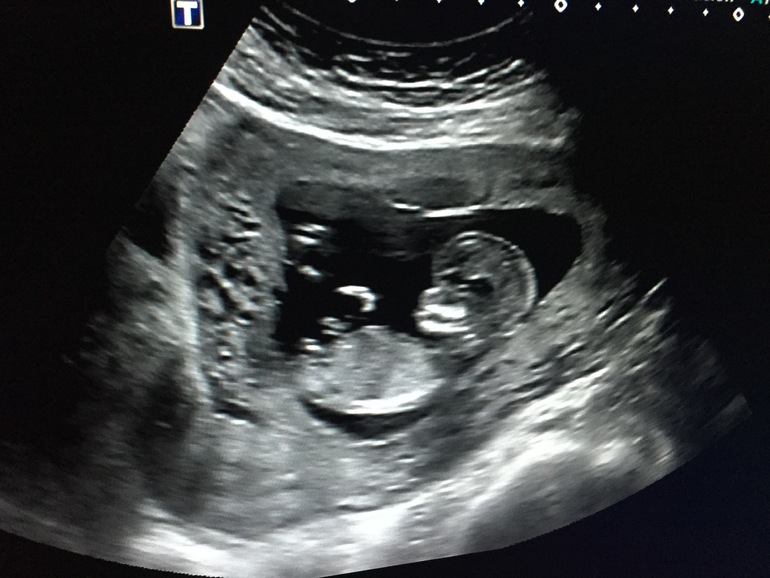

А посмотри на картинке, если тебе распечатывали, ее обычно хорошо видно. Беленькая такая, маленькая